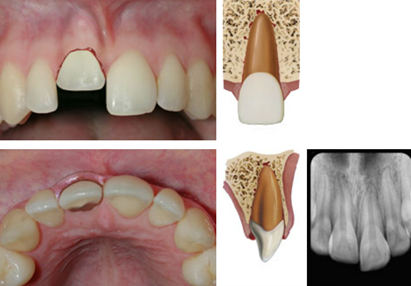

dx extrusion

A

Appears elongated

Excessively mobile

Usually lack of response except for teeth with minor displacements. The test is important in assessing risk of healing complications. A positive result to the initial test indicates a reduced risk of later pulp necrosis.

* In immature, not fully developed teeth, pulpal revascularization usually occurs. In mature teeth pulp revascularization sometimes occurs.

Occlusal, PA and 2 eccentric exposures from different horizontal angulations

Inc PA ligament space